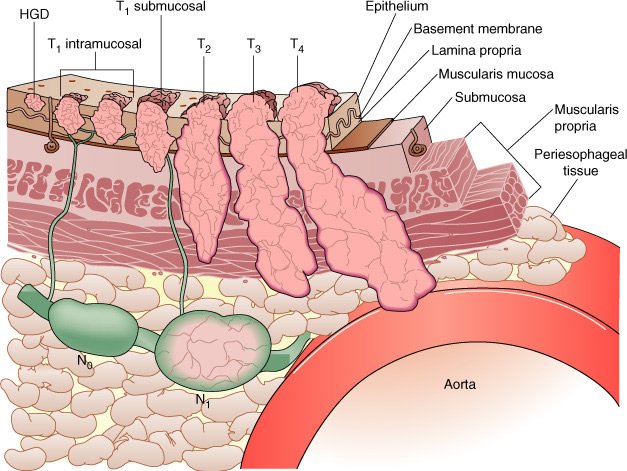

O estádio do tumor é classificado mais frequentemente conforme o sistema proposto pela American Joint Committee on Câncer (AJCC). Este sistema é baseado no TNM, onde "T" (tumor) indica o grau de invasão progressivo (de 1 a 4) do tumor na parede do esófago. O "N" é o envolvimento linfonodal, e "M* representa as metástases a distância.

A condição do tumor primário (T) é definida pela profundidade da invasão tumoral. A condição ganglionar (N) é definida pela ausência (N0) ou presença (N±) de metástases regionais. HGD = displasia de alto grau

O estadiamento adequado é importante porque a sobrevida está intimamente relacionada ao estádio de T e N, e com a avaliação de invasão do tronco celíaco. Cânceres T4, que não se beneficiam com a operação, podem ser adequadamente avaliados por USE. Sobrevida de 5 anos, conforme estádios:

Tumores esofágicos precoces comprometem a mucosa (T1m) ou a submucosa (T1sm). Tumores T1m estão associados a menos de 5% de comprometimento linfonodal comparados com T1sm, que apresentam de 30% a 40%.

A sobrevida global para tumores T1 é de 90% em 5 anos. Tumores precoces comprometendo a mucosa (T1m) podem ser ressecados endoscopicamente em pacientes que não são candidatos à operação ou recusam-se à esofagectomia. Candidatos ideais para ressecção mucosa endoscópica compreendem cânceres intramucosos de tamanho limitado (menores que 2 cm, com menos de três quartos de comprometimento circunferencial), com menos de quatro áreas de comprometimento tumoral.

O transdutor de ultra-som de alta frequência pode diferenciar mais precisamente T1m de T1sm quando comparado à USE tradicional.